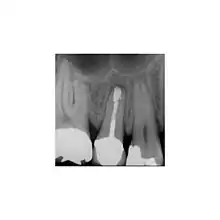

- Préparation et remplissage de terminaison radiculaire

La préparation de la terminaison radiculaire est pratiquée après la résection de l'apex. Cela doit suivre les contours du système canalaire et être dans l'axe du (des) canal(aux). L'objectif du remplissage de terminaison canalaire est de remplir cette cavité et de fermer toute communication du canal radiculaire aux tissus péri radiculaires. Un matériau de remplissage est placé dans la cavité de la terminaison radiculaire. L'amalgame n'est plus le matériau de choix.